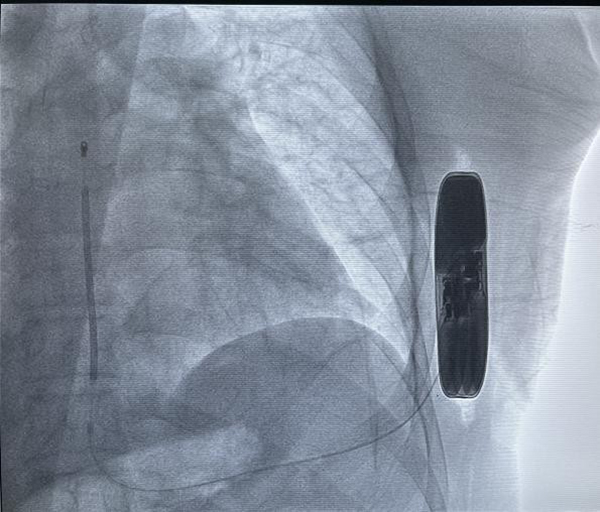

SICD主要由脈沖發(fā)生器、電極導(dǎo)線組成,與頸靜脈植入型心律轉(zhuǎn)復(fù)除顫器(TV-ICD)。不同的是,SICD的脈沖發(fā)生器經(jīng)皮下置于左側(cè)胸壁,電極是由兩個(gè)感知電極及一個(gè)電擊線圈組成,經(jīng)皮下置于胸骨旁。作為全皮下心臟除顫系統(tǒng),SICD可在一定程度上避免與靜脈導(dǎo)線相關(guān)的圍手術(shù)期及其長期并發(fā)癥,且手術(shù)過程不需要在透視下進(jìn)行。SICD的適應(yīng)人群主要包括:伴有靜脈畸形或梗阻不適合經(jīng)靜脈行心臟轉(zhuǎn)復(fù)除顫器的兒童、感染風(fēng)險(xiǎn)大及有猝死風(fēng)險(xiǎn)的年輕心律失常患者(如Brugada綜合征、長QT綜合征等)。